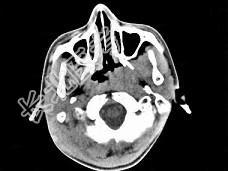

- 单项选择题男,17岁, 自诉鼻涕中带血3个月,伴耳闷、听力减退, 无发热。如图所示鼻咽部病灶最可能的诊断为 ( )

C、鼻咽癌